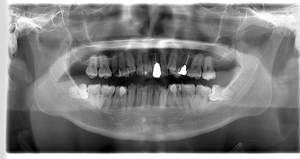

- 抜歯前写真(レントゲン、CT等)

| 抜歯内容 | 下顎の親知らずの抜歯希望の患者様です。 智歯周囲炎となっており、初診時では麻酔が効きづらい旨をお話しし、初診時は抗生物質をお出ししました。1週間後、ある程度歯肉の炎症がとれたことを確認して抜歯を行いました。 麻酔を行い、遠心(親知らずの奥側)歯肉と、手前の歯の頬側の歯肉を切開しました。 歯茎を開いて、手前の歯と引っかかっている部分をカットしました。 その後、骨からでている歯冠部(頭の部分)をカットしました。 その後へーベルで歯根(骨に埋まっている部分)を脱臼し、抜歯を終えました。 切開した歯茎を3針縫って、治療終了となりました。 歯茎を切ったため、3日ほど腫れぼったい感じがあったようですが、痛みはほとんどなく、治癒に向かいました。 |

CTで親知らずと神経(下歯槽管)の位置を確認しました。

親知らずと神経は一定の距離があり、麻痺などのリスクがほとんどないと判断できます。